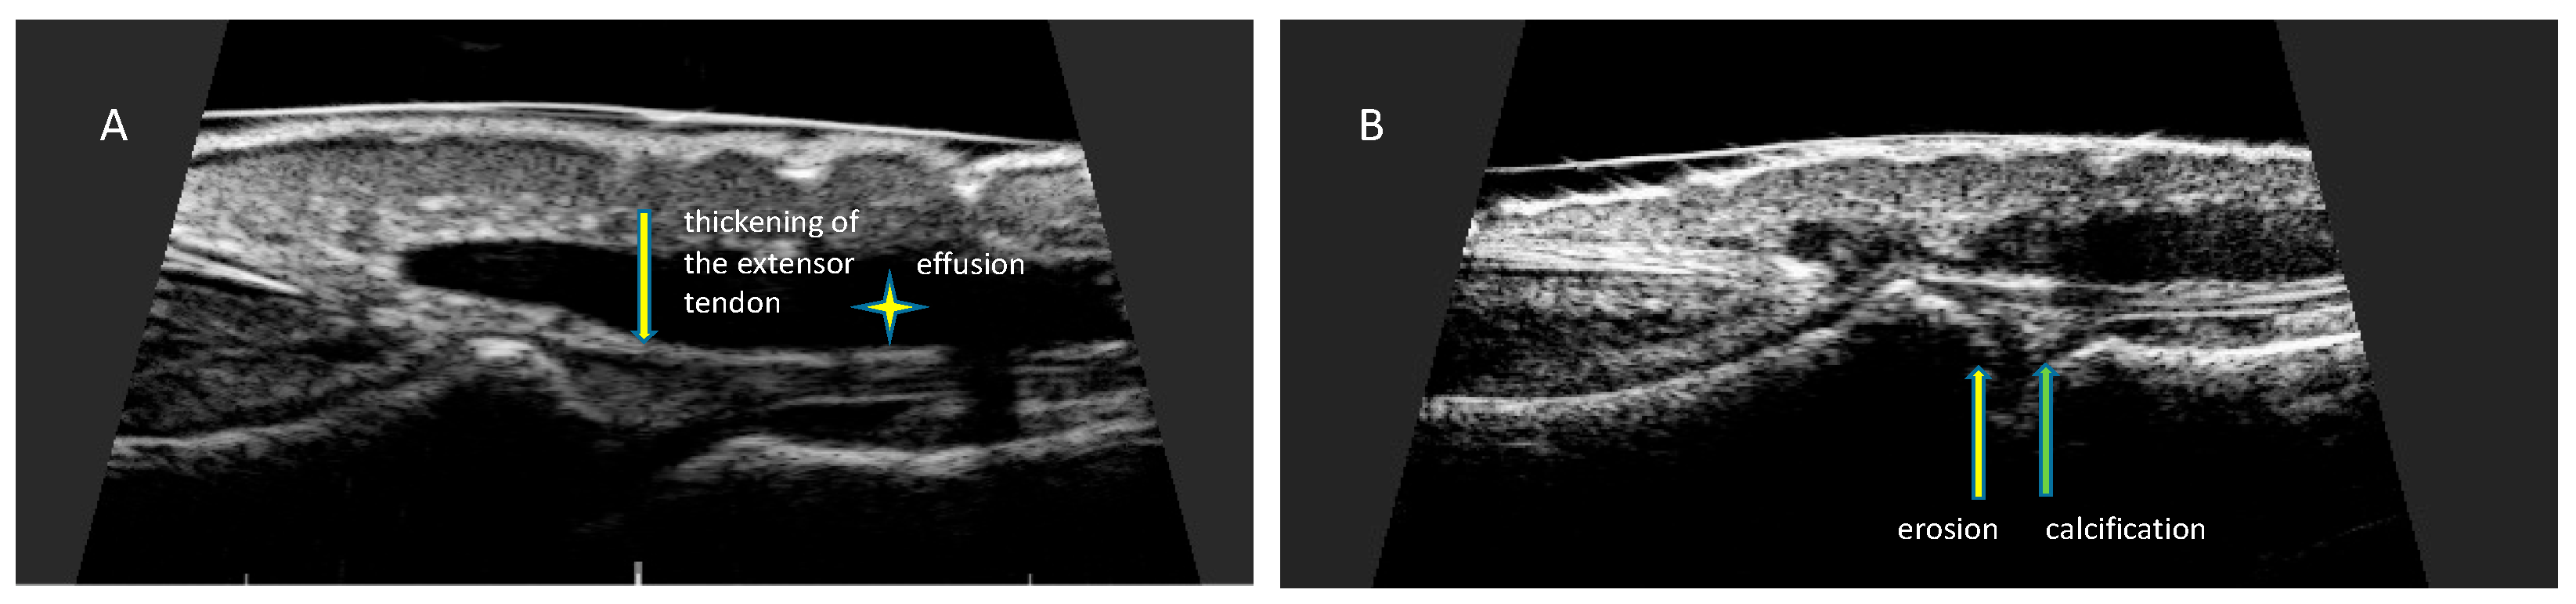

7. Ultrasonographic Changes of the Nail Apparatus in Psoriasis and Psoriatic Arthritis